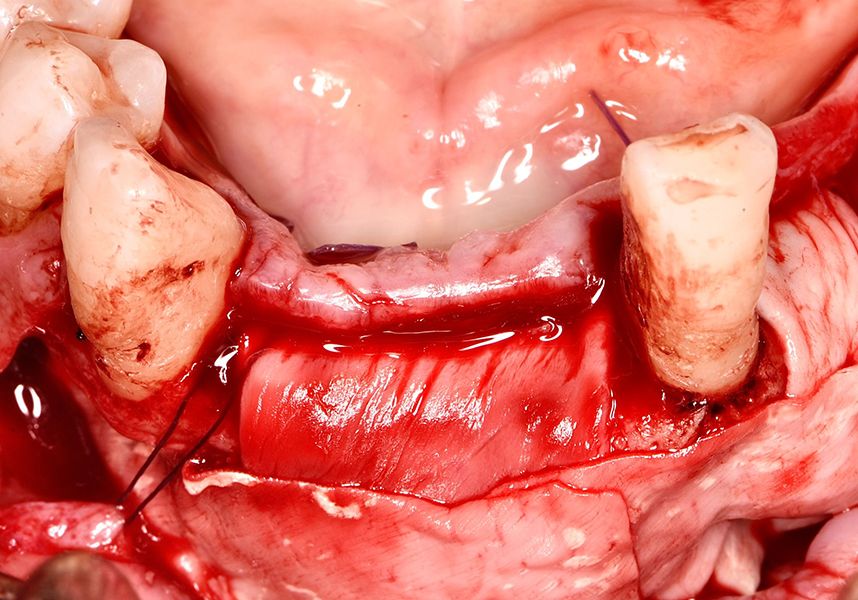

The patient was anesthetized and a flap was made from the distal area of tooth 43 up to 36. Then two Avinent Biomimetic Ocean IC implants of 3.5x10 were inserted in positions 32 and 42.

Respecting the three-dimensionally correct position of the implant led to bone fenestration, leaving the apical part of the apex of the implant exposed almost to the mid-point of its length at 42 and a third in 32.

To treat the defect, bone regeneration was carried out simultaneous to the surgical process, with an autologous bone graft from the patient. In the internal part of the graft we used autologous cortical bone obtained by scraping (Safescraper) and from the biological drilling, at low revolutions and without irrigation, from the other implant beds. In the external layer of the regeneration we used a xenograft (Genoss, Osteogenos) and this was covered with a reabsorbable collagen barrier membrane (Evolution STD, Osteogenos).

The membrane was sutured with PGA reabsorbable suture to the periosteum to secure it, thus avoiding subsequent reentry to remove fixings such as tacks.